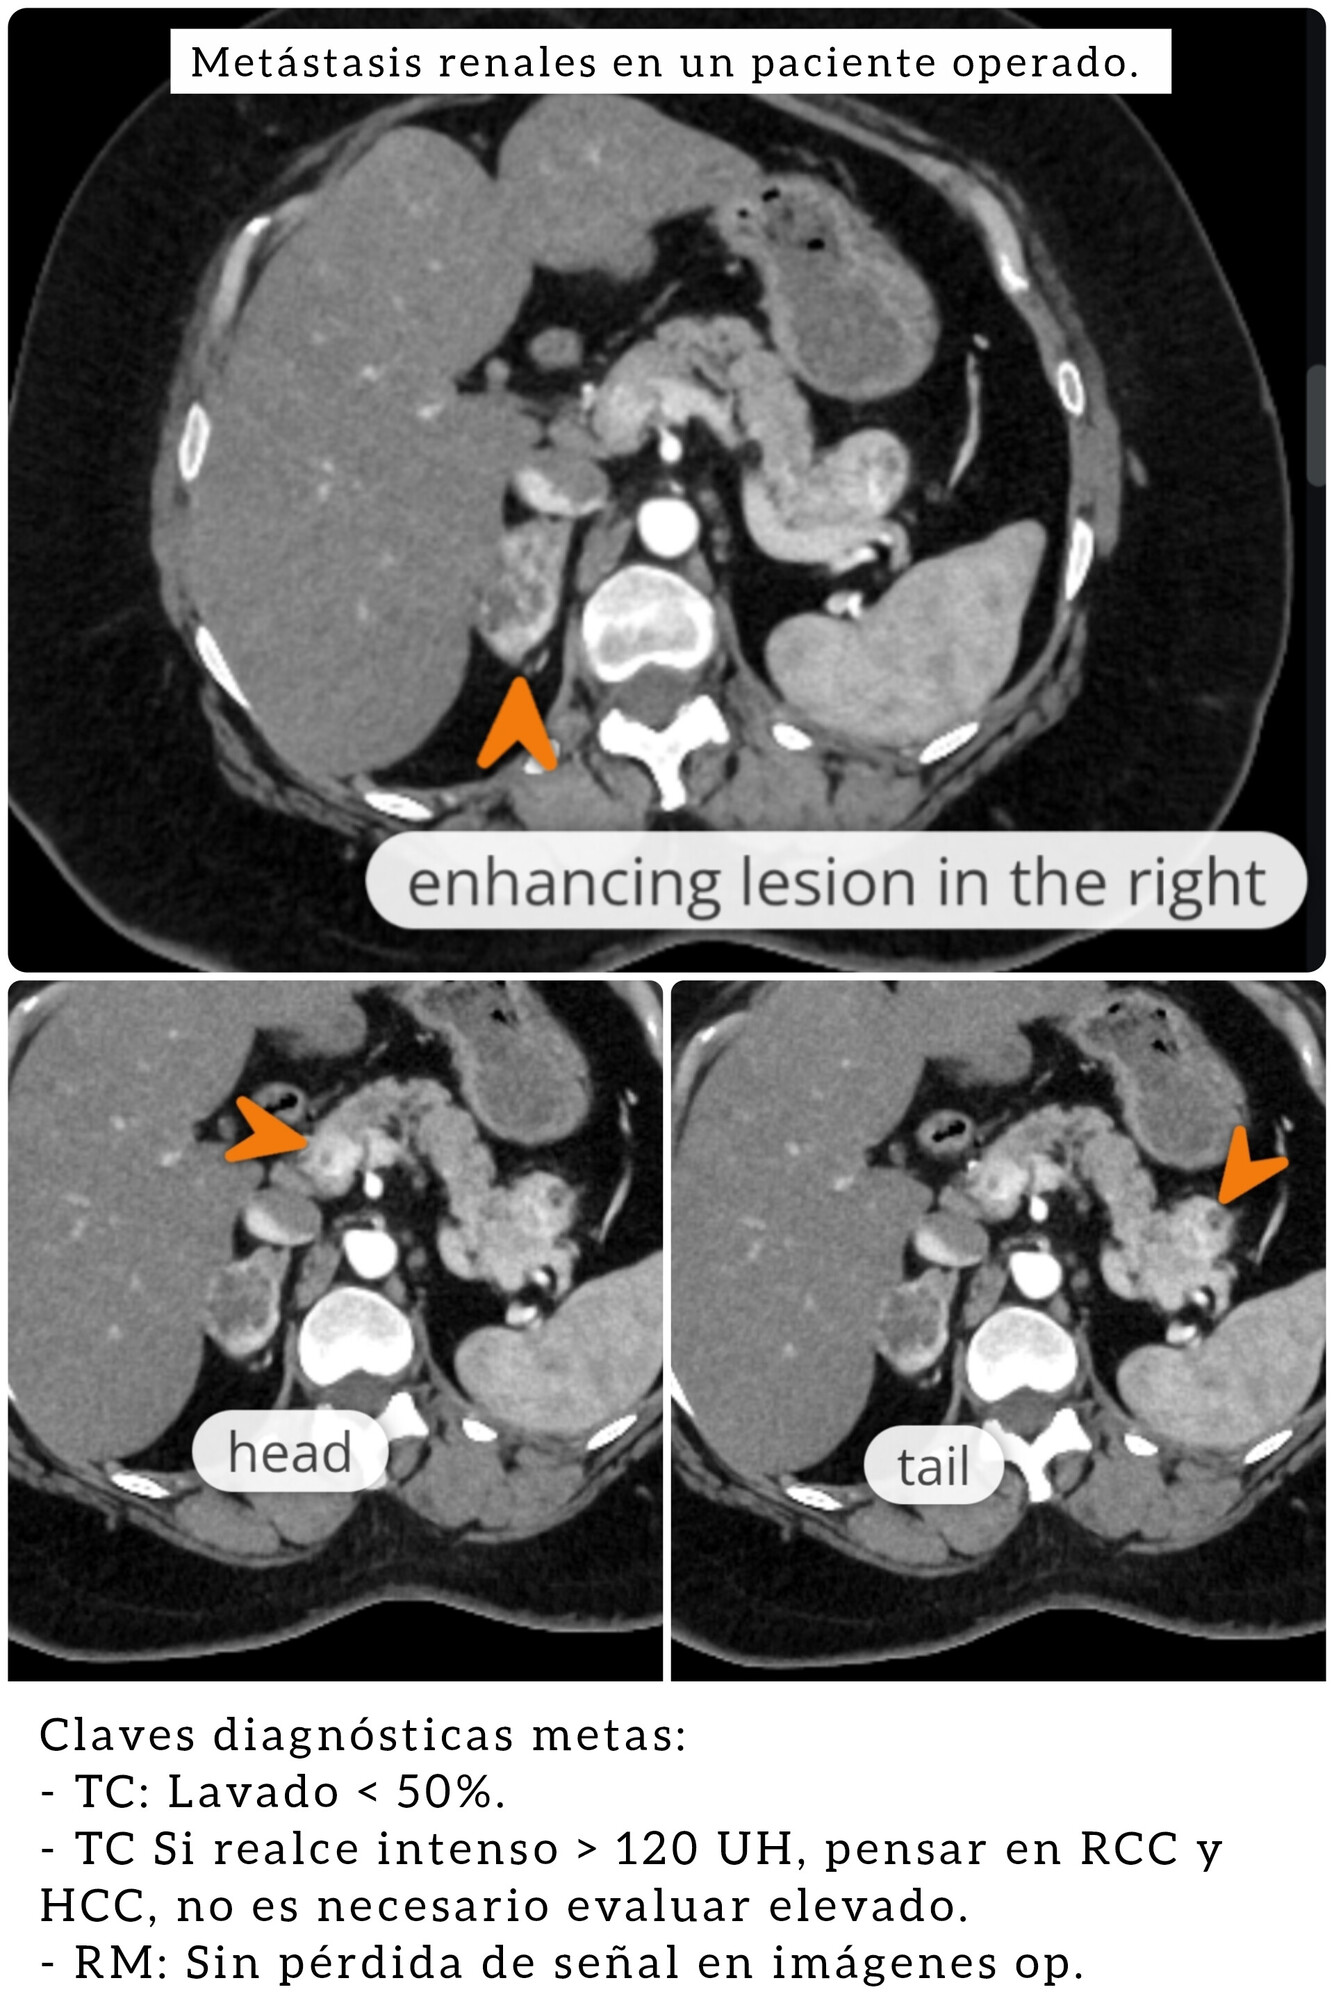

Metástasis suprarrenales.

Las metas son la causa más común de masas suprarrenales bilaterales.

DDx: Feocromocitoma, bilateral en un 10% de los casos.